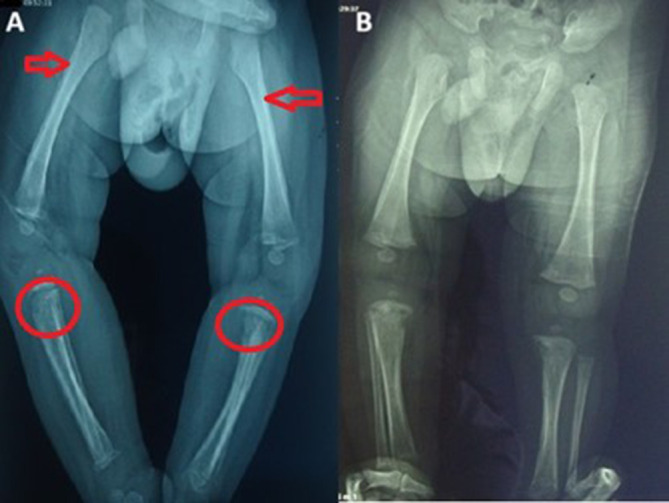

二期梅毒是由梅毒螺旋体引起的性传播感染的一个阶段,通常在成人中出现一系列症状。然而,当这种情况影响到婴儿时,它就变成了一种罕见而严重的医学问题。这篇文章探讨了一个独特的婴儿二期梅毒病例,强调了诊断的挑战,治疗的选择,以及早期干预的重要性。

Secondary syphilis, a stage of sexually transmitted infection caused by Treponema pallidum, typically presents with a range of symptoms in adults. However, when this condition affects an infant, it becomes a rare and serious medical concern. This article explores a unique case of secondary syphilis in an infant, highlighting the diagnostic challenges, treatment options, and the importance of early intervention.